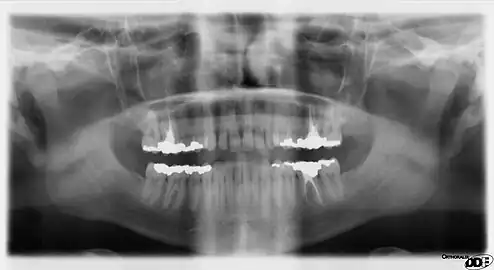

A panoramic radiograph is a panoramic scanning dental X-ray of the upper and lower jaw. It shows a two-dimensional view of a half-circle from ear to ear. Panoramic radiography is a form of focal plane tomography; thus, images of multiple planes are taken to make up the composite panoramic image, where the maxilla and mandible are in the focal trough and the structures that are superficial and deep to the trough are blurred.

Orthopantomograms (OPTs) are used by health care professionals to provide information on:

- Impacted wisdom teeth diagnosis and treatment planning - the most common use is to determine the status of wisdom teeth and trauma to the jaws.

- Periodontal bone loss and periapical involvement.

- Finding the source of dental pain, and when carrying out tooth-by-tooth diagnosis.

- Assessment for the placement of dental implants

- Orthodontic assessment. pre and post operative

- Diagnosis of developmental anomalies such as cherubism, cleido cranial dysplasia

- Carcinoma in relation to the jaws

- Temporomandibular joint dysfunctions and ankylosis.

- Diagnosis of osteosarcoma, ameloblastoma, renal osteodystrophy affecting jaws and hypophosphatemia.

- Diagnosis, and pre- and post-surgical assessment of oral and maxillofacial trauma, e.g. dentoalveolar fractures and mandibular fractures.

- Salivary stones (Sialolithiasis).

- Other diagnostic and treatment applications.[2]